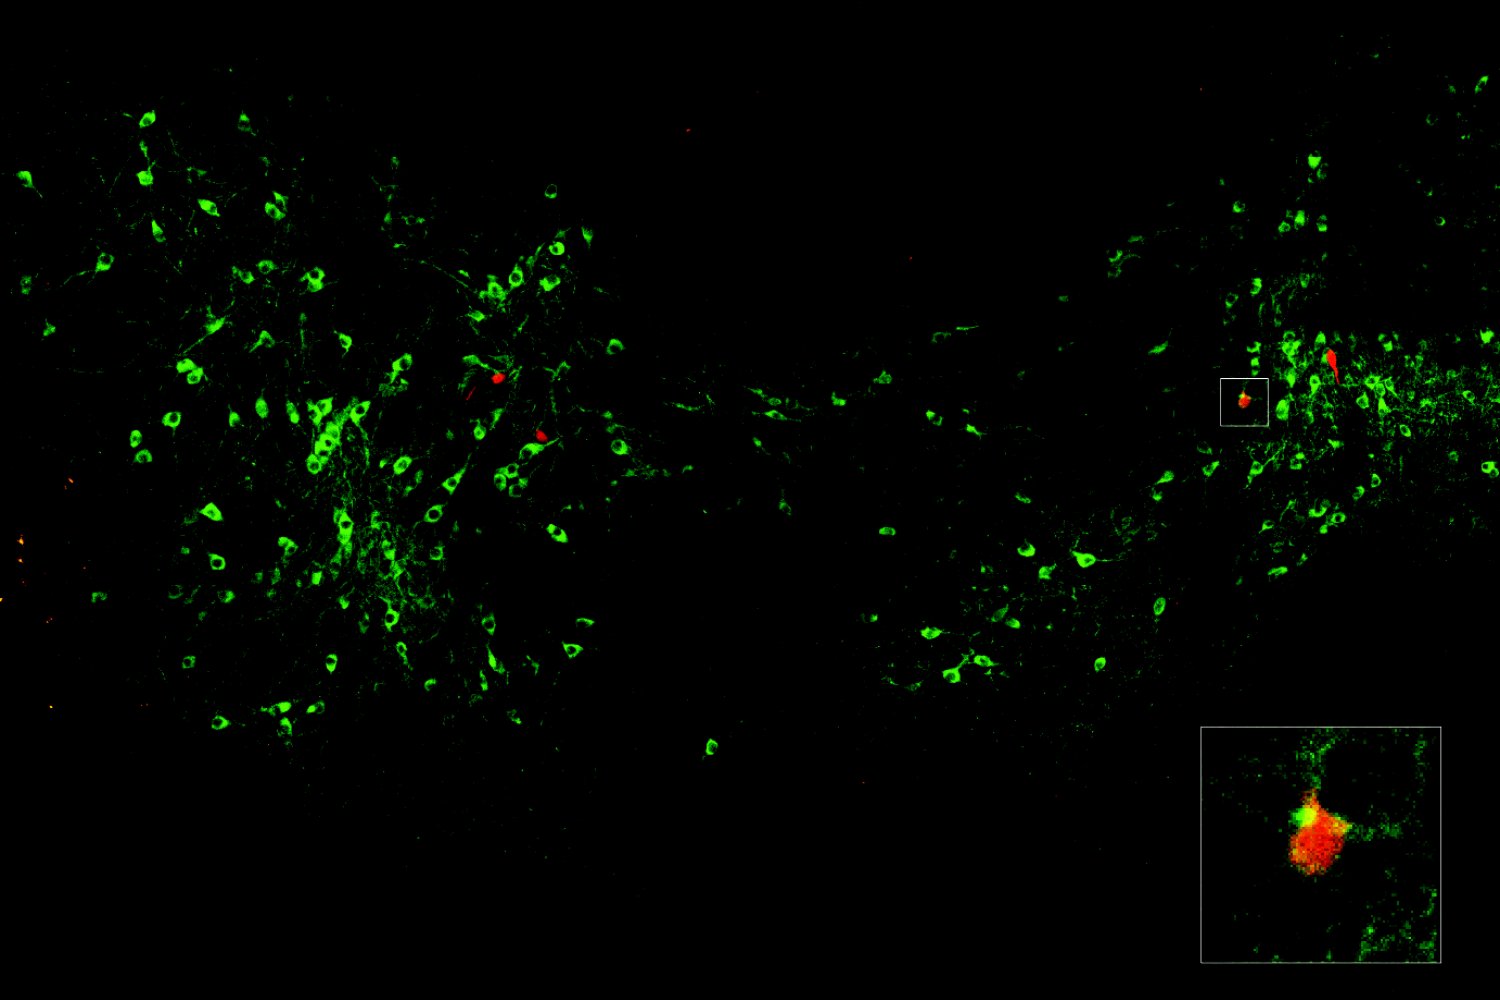

Dopamine signals when a fear can be forgotten

Dopamine signals when a fear can be forgotten

Dopamine signals when a fear can be forgotten

Dopamine signals when a fear can be forgotten

Dopamine signals when a fear can be forgotten